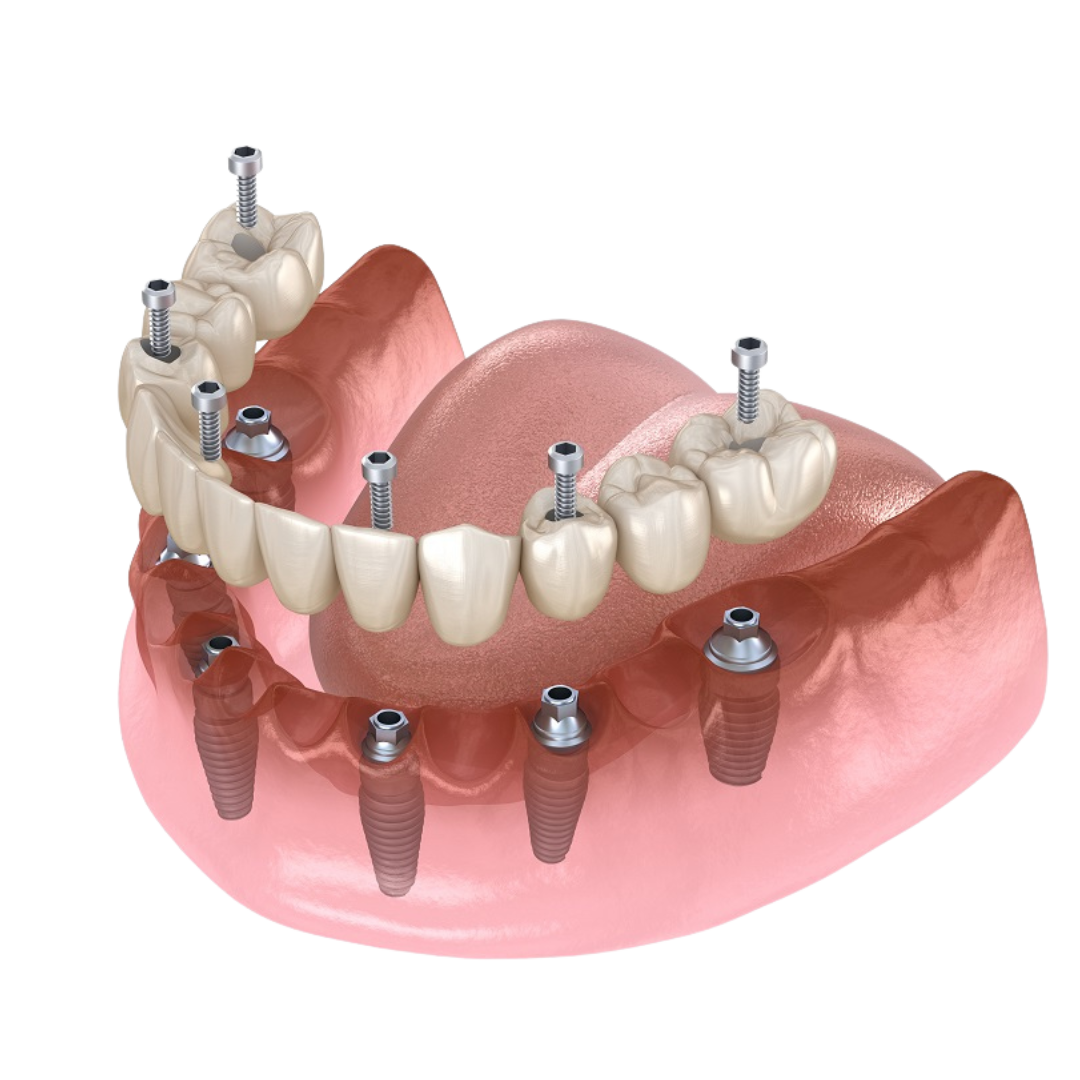

Immediate load implants: a new smile in just one day

Immediate load implants

Restore your smile in record time. In selected cases, we place both the implant and the provisional prosthesis on the same day, with no need to wait for months.